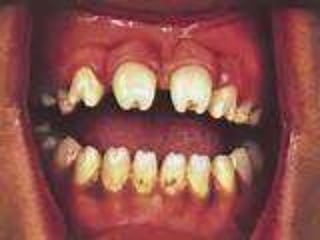

 An obviouscause in the mouth (usually) such as a decayed tooth.  Teeth that are tender to percussion, which may develop as the condition progresses  Loosening of teeth, which may develop as the condition progresses.  Pus may later be visible, which exudes from around the necks of teeth, from an open socket, or from other sites within the mouth or on the skin over the involved bone.  Fetid odor.

 SYPHILITIC OSTEOMYELITIS  Syphilis isa chronic granulomatous disease which is caused by the spirochete Treponema pallidum. It is a contagious venereal disease which leads to many structural and cutaneous lesions. Acquired syphilis is transmitted by direct contact whereas congenital syphilis is transmitted in utero. In congenital syphilis, the teeth are hypoplastic, that is, the maxillary incisors have screwdriver-shaped crowns with notched incisal edges (Hutchinson's teeth) and the molars have irregular mass of globules instead of well-formed cusps ("mulberry